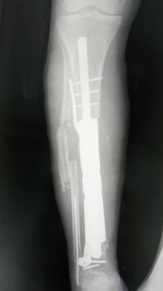

2025年12月,周翔再次到江门市中心医院指导这场关键手术。手术当天,医护团队按照术前规划,有条不紊地开展操作:小心翼翼地掀起之前移植的皮瓣,避免损伤吻合的血管;取出临时填充的骨水泥和固定钢板;在胫骨远近端进行精准截骨,一次顺利完成并在可控制范围之内;随后,将定制好的3D打印金属假体精准植入,调整位置后用螺丝固定牢固。

与之前的手术不同,这场私人定制式的假体植入手术仅用了不到2小时就顺利完成。“术前我们做了充分的规划,假体的尺寸、形态都完全贴合患者的骨骼,所以术中操作非常顺利,没有出现任何意外。”陈元庄介绍,由于术前准备充分,手术创伤也远远小于传统方案,大大减轻了吴大爷的痛苦。

△3D打印定制式胫骨金属假体(可拆分)。